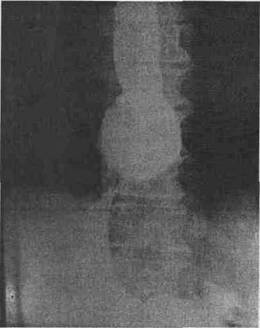

H-H mari, fixate, se evidentiaza usor ca o masa opaca rotunda sau ovala, situata imediat supradia-fragmatic stang, ,,coafand' polul superior al fornixu-lui si legata de acesta printr-un colet care traver-seaza hiatusul, avand pliuri gastrice, paralele (fig. 2). Alteori apar si semne radiologice ale asa-zisului ,,ulcer de colet'. Din profil imaginea apare dispusa retrocardiac, iar esofagul toracic este flexuos.

Fig. 2 - Tranzit baritat eso-gastric in procubit cu sac cu nisip sub epigastru: H-H de alunecare mare, fixata cu RGE.